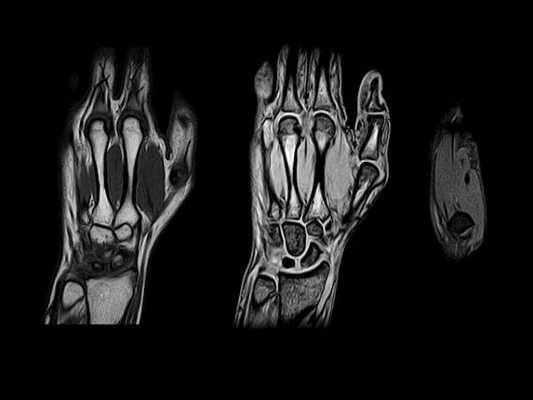

МРТ сухожилий запястья в продольной проекции в норме

На рисунке в аксиальной проекции показаны сухожилия в проксимальном отделе запястья. Сухожилия мышц-разгибателей проходят под удерживателем разгибателей, а сухожилия сгибателей на этом уровне запястья расположены проксимальнее удерживателя сгибателей. На соответствующем МР-срезе все сухожилия создают сигнал низкой интенсивности. На рисунке в аксиальной проекции показаны сухожилия в запястном канале. Сухожилия глубокого сгибателя пальцев направляются к мизинцу, безымянному, среднему и указательному пальцам параллельно друг другу (от медиальной стороны к латеральной). Из сухожилий поверхностного сгибателя пальцев два глубоких сухожилия направляются к среднему и безымянному пальцам и два поверхностных сухожилия проходят к мизинцу и указательному пальцам. Сухожилие длинного разгибателя большого пальца проходит над сухожилием короткого лучевого разгибателя запястья (КЛуРЗ). На соответствующей рисунку аксиальной МРТ показаны сухожилия в запястном канале. Обратите внимание на феномен «магического угла» на ДРБП в месте его прохождения над КЛуРЗ. Сухожилие находится под углом 55° к главному магнитному полю, что приводит к потере нормального низкоинтенсивного сигнала. На первой из шести отобранных аксиальных МР-томограмм показан ход сухожилий и их отношение к окружающим костным структурам. Удобным костным ориентиром служит бугорок Листера, разделяющий II и III каналы разгибателей. Удерживатель разгибателей удерживает сухожилия разгибателей в шести отдельных каналах. Срединный нерв имеет округлую форму и лежит кнаружи и латеральнее сухожилий сгибателей пальцев. Обратите внимание на феномен «магического угла» на ДРБП в месте ее пересечения с КЛуРЗ. Удерживатель сгибателей огибает запястный канал от бугорка ладьевидной кости до крючка крючковидной кости. Его поверхностные волокна образуют крышу канала Гийона. Удерживатель сгибателей прикрепляется к гребню кости-трапеции с латеральной стороны и крючку крючковидной кости — с медиальной. При трехмерной КТ реконструкции с наложением мягких тканей показаны границы анатомической табакерки: длинный разгибатель большого пальца (III канал), пересекает запястье с медиальной стороны к латеральной над сухожилиями короткого и длинного лучевых разгибателей запястья (II канал), образуя заднюю границу, тогда как сухожилия длинной мышцы, отводящей большой палец и короткого разгибателя большого пальца (I канал) образуют переднюю границу. Через анатомическую табакерку проходят лучевой нерв и его поверхностная ветвь, а также одноименные артерия и вена. На МР-томограмме анатомическая табакерка показана в аксиальной проекции. При трехмерной КТ-реконструкции с наложением мягких тканей показан мышечно-сухожильный перекрест короткого разгибателя большого пальца и длинной мышцы, отводящей большой палец, с сухожилиями длинного и короткого лучевых разгибателей запястья, продолжающийся в дистально-латеральном направлении непосредственно проксимальнее удерживателя разгибателей. На аксиальных МР-томограммах их сложное взаимное расположение показано на поперечном срезе. На нижней правой МР-томограмме показан дистальный отдел предплечья: короткий разгибатель большого пальца и длинная мышца, отводящая большой палец, лежат кнаружи и немного кзади от сухожилий короткого и длинного лучевых разгибателей запястья. На нижней левой и верхней правой МРТ короткий разгибатель большого пальца и длинная мышца, отводящая большой палец, пересекают сверху длинный и короткий лучевые разгибатели запястья и располагаются на латеральной поверхности лучевой кости. На верхней левой МР-томограмме—наиболее дистальном из этих срезов, на уровне бугорка Листера, перекрест заканчивается, и сухожилия занимают свое положение на запястье.

Первая из 20 последовательных Т1-взвешенных томограмм запястья в продольной проекции с направлением срезов от локтевой (медиальной) стороны к лучевой (латеральной). Сухожилие ЛоРЗ пересекает дистальный отдел локтевой кости в локтевой борозде ЛоРЗ. Мышца, отводящая мизинец—самая медиальная и передняя мышца гипотенара. Гороховидно-пястная связка соединяет гороховидную кость с V пястной костью. Она прилежит к гороховидно-крючковидной связке (следующая томограмма). Хорошо виден гороховидно-трехгранный суставной карман. Мышцы гипотенара менее прочные в области отхождения их от удерживателя сгибателей. Сухожилие локтевого сгибателя запястья прикрепляется к гороховидной кости. Локте-трехгранная связка отходит от ладонной лучелоктевой связки и прикрепляется к ладонной поверхности трехгранной кости. Локтевые нерв и артерия проходят в канале Гийона латеральнее и дистальнее гороховидной кости. Выступает крючок крючковидной кости. Треугольный хрящевой диск (ТХД) визуализируется в виде диска с низкоинтенсивным сигналом между головкой локтевой кости и трехгранной костью. Ладонная и тыльная лучелоктевые связки вместе с ТХД и прилежащими структурами образуют треугольный фиброзно-хрящевой комплекс. Внешние и внутренние связки иногда сложно выделить в качестве отдельных образований. Указатели направлены к визуализируемым связкам или месту возможного обнаружения связки. Тыльная межзапястная связка—основная связка, стабилизирующая тыльный отдел запястья, но визуализируется только на ограниченном участке. Сухожилия поверхностного и глубокого сгибателей пальцев проходят под горизонтально расположенным удерживателем сгибателей. Сухожилия разгибателя пальцев проходят через IV канал разгибателей и фиксируются удерживателем разгибателей. На ладонной поверхности можно увидеть пучки лучеладьевидно-локтевой и короткой лучеполулунной связок. На задней поверхности можно увидеть тыльную лучезапястную связку, отмечена область тыльной межзапястной связки. Характерный наклон в ладонную сторону дистального отдела лучевой кости обусловлен тем, что тыльный край лучевой кости расположен более дистально, чем ладонный (12°). Центральная ость запястья образована основанием III пястной кости, головчатой и полулунной костями, а также полулунной ямкой лучевой кости. Сухожилие разгибателя указательного пальца—самое латеральное сухожилие IV канала разгибателей. Сухожилие мышцы, противопоставляющей большой палец, на этом срезе отходит от удерживателя сгибателей. Срединный нерв расположен поверхностнее сухожилия длинного сгибателя большого пальца и глубже удерживателя сгибателей. Длинная лучеполулунная связка отходит от лучевой кости непосредственно латеральнее лучеладьевидной и короткой лучеполулунной связок. Сухожилие длинного разгибателя большого пальца лежит медиальнее бугорка Листера и в дистально-латеральном направлении на пути к большому пальцу пересекает сухожилия длинного и короткого лучевых разгибателей запястья. На этом срезе визуализируются сочленения трапециевидной, головчатой и ладьевидной костей между собой. Сухожилие длинного сгибателя большого пальца проходит под локтевым нервом непосредственно медиальнее сухожилия лучевого сгибателя запястья. Сухожилие короткого лучевого разгибателя запястья (КЛуРЗ) прикрепляется к основанию III пястной кости. Сухожилие лучевого сгибателя запястья проходит поверхностнее бугорка ладьевидной кости и прикрепляется к основанию II пястной кости. Лучеладьевидно-головчатая связка отходит от края ладонной поверхности лучевой кости. Сухожилие лучевого сгибателя запястья проходит поверхностнее бугорка ладьевидной кости и прикрепляется к основанию II пястной кости. Сухожилие короткого лучевого разгибателя запястья (КЛуРЗ) пересекает тыл запястья и прикрепляется к тыльной стороне основания III пястной кости. Наиболее латеральный отдел лучеладьевидно-головчатой связки иногда называют лучевой коллатеральной связкой. Сухожилие длинного лучевого разгибателя запястья (ДЛуРЗ) пересекает тыл запястья и прикрепляется к основанию II пястной кости. Лучевая артерия, поверхностная ветвь лучевого нерва и латеральная подкожная вена руки проходят через анатомическую табакерку, ограниченную костью-трапецией, ладьевидной костью и шиловидным отростком лучевой кости. Сухожилия длинной мышцы, отводящей большой палец и короткого разгибателя большого пальца, образуют ладонный край анатомической табакерки, а сухожилие длинного разгибателя большого пальца формирует ее тыльный край. Сухожилия длинной мышцы, отводящей большой палец и короткого разгибателя большого пальца, образуют дистальный край анатомической табакерки после соединения непосредственно дистальнее I запястно-пястного сустава. Лучевая артерия разветвляется и продолжается в дистальном направлении, образуя глубокую ладонную дугу. Сухожилия длинной мышцы, отводящей большой палец и короткого разгибателя большого пальца соединяются в месте прикрепления к основанию I пястной кости.